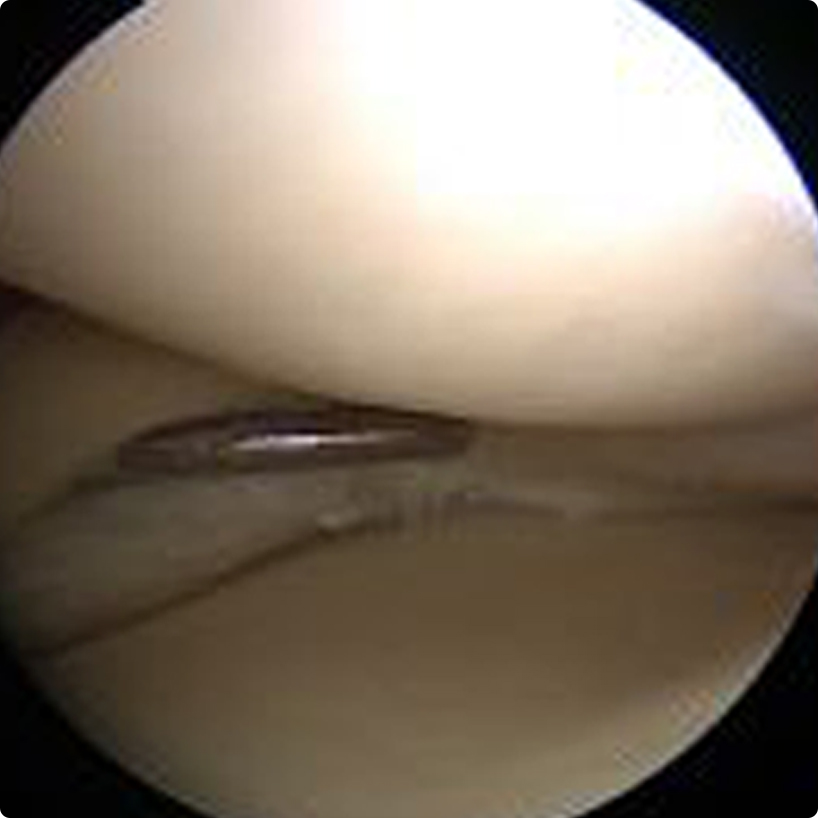

Tanı konulduktan sonra hastanın şikayetlerinin ciddiyeti, günlük hayatındaki işlevlerine etkisi göz önüne alınarak tedavisi yapılır. Genellikle acil olan durumlar (örneğin diz ekleminin kilitlenmesi, hareket ettirilememesi) dışında öncelikle ağrı kesici ve yangı giderici ilaçlar, istirahat, egzersiz, soğuk uygulama ve aktivitelerin düzenlenmesini içeren bir tedavi verilir. Bu tedavi ile başarı sağlanamadığında özellikle genç yaş grubundaki yırtıklarda cerrahi tedavi gerekir. Cerrahi tedavi günümüzde eklemin kamerayla görüntülenmesi eşliğinde yapılan “artroskopik-kapalı” yöntemlerle yapılır.

Bu yöntemle diz ekleminin içi görüntülenerek tanı doğrulanır, ek sorunlar varsa tespit edilir ve aynı anda tedavileri yapılabilir.

Amaç mümkün olduğunca fazla sağlam menisküs dokusu bırakarak yırtık kısmın çıkarılması, veya eğer yırtık kanlanan çevresel bölgedeyse dikişlerle tamir edilmesidir.